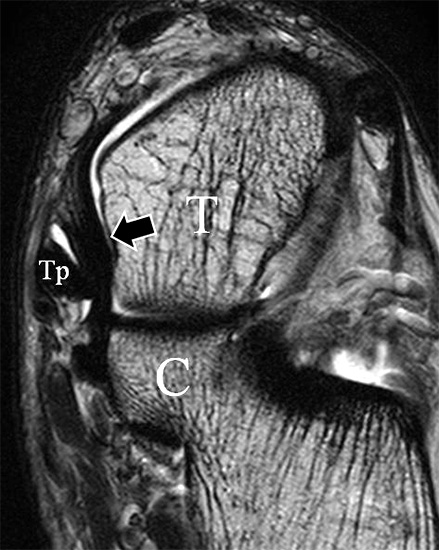

Das Ligamentum fibulotalare anterius entspricht einer bifaszikulären Struktur (Abb. 2 a) mit interponierendem fibrovaskulärem Gewebe (S. K. Sarrafian (ed). 2003). Es gibt jedoch Variationen der Ligamentanatomie. In 55% liegt das LFTA als bifaszikuläres Band (Abb. 2 a), in 9% als monofaszikuläre Bandstruktur (Abb. 2 b) und in 36% als multifaszikuläre, striäre Variante (Abb. 2 c) vor 3.

Das LFTA verbindet die antero-inferiore Fibulaspitze mit dem Processus lateralis tali und inseriert hier an einem oder zwei kleinen Tuberkeln 3. Der in Neutralposition horizontale Verlauf erleichtert die kernspintomographische Darstellung in dieser Standardebene. Das LFTA weist durchschnittlich eine Breite von knapp über 2 mm auf 4. Somit sind bei einer Routinedarstellung in 3 mm Schichtdicke Anschnittsphänomene, die die Diagnostik erschweren, regelmäßig anzutreffen. Dementsprechend sind auch die ligamentären Subfaszikel nicht zu differenzieren. In koronarer Darstellung ist dies aufgrund der hohen Auflösung in der Schichtebene jedoch möglich (Abb. 2 a-c), wobei hier wiederum eine Integritätsbeurteilung des Bandes erschwert ist. Unter Verwendung hochauflösender Techniken im Millimeterbereich (Schichtdicke) sind hingegen auch in der axialen Ebene die subfaszikulären Strukturen zu beurteilen (Abb. 3).